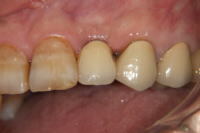

(術後)

症例1-03.jpg

1次手術から3ヶ月後、

土台をセットしたところ。

1次手術から4ヵ月後、

最終的な冠をセットした

ところ。